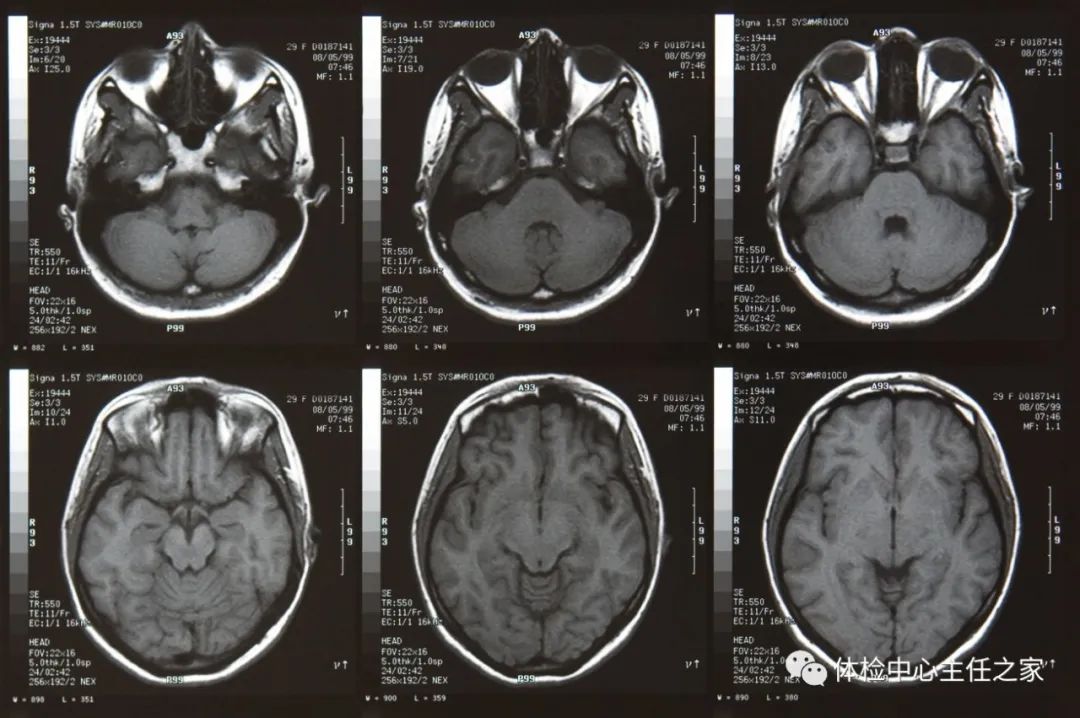

MRI利用强大的磁场,让身体中的水分振动起来,再平静下来,感受振动,成像后可以观察到正常组织与患病部位之间的差异。所以,MRI也被戏称为“摇摇看的检查”。MRI可以随意进行任何角度的切层,且无辐射。对颅脑、脊柱和脊髓等的解剖和病变的显示,都优于CT。MRI对病变组织的敏感度亦优于CT,尤其是通过MRI,关节、肌肉、中枢神经系统等软组织的检查结构更清晰。MRI对脊柱、关节、肿瘤、感染性疾病、淋巴结和血管结构之间的相互鉴别,也有独到的优势。

但是,有些方面MRI不如CT,比如对肺部、骨骼结构的细节表现及骨折等,所以有时骨科医生会要求患者两者都要检查。